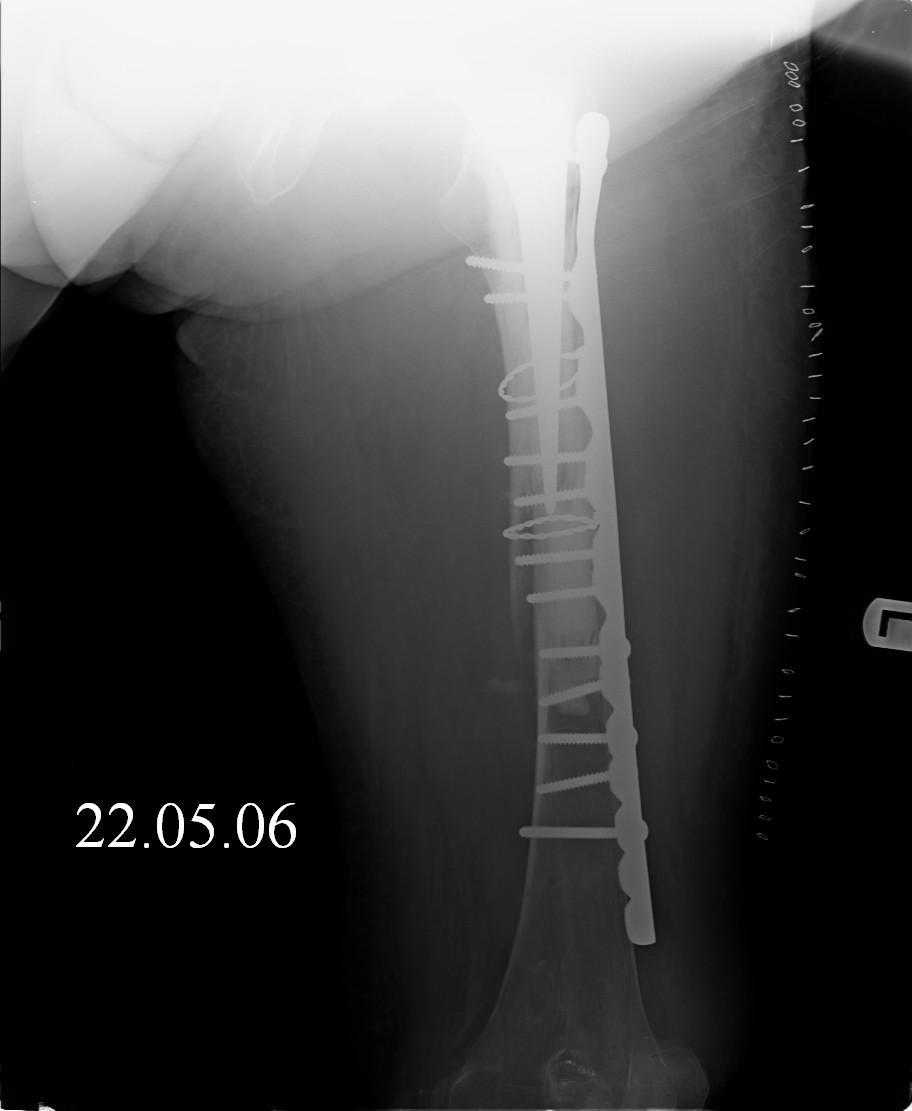

[Ortho] Перипротезный перелом

Hello! This is just illustration in one of the choice of treatment